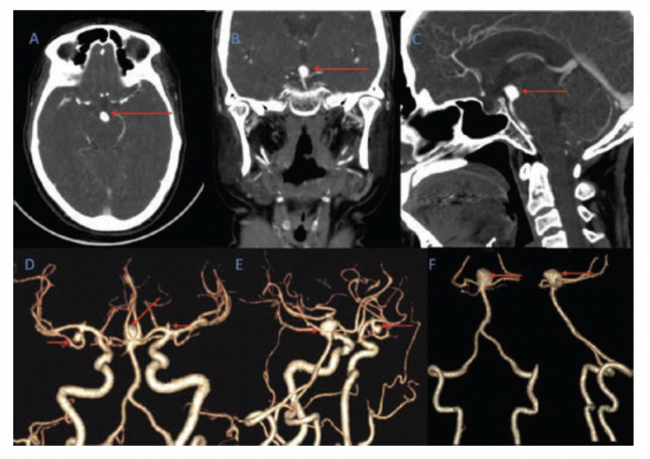

A 46-year-old woman presented with sudden onset headache associated with 2 to 3 episodes of vomiting and giddiness. On examination, her Glasgow Coma Scale (GCS) was 15/15 and power in all four limbs was 5/5. A non-contrast CT brain scan (Figure 1) revealed a diffuse SAH more predominant in the basal cisterns on the left side with intraventricular extension into the 4th ventricle (Fisher grade 4). There was no hydrocephalus. A CT angiogram (Figure 2) and diagnostic cerebral angiogram (Figure 3) demonstrated 3 intracerebral aneurysms in the following locations: inferior division of the right middle cerebral artery (MCA), 4.3 x 5 x 3.6 mm (AP x ML x CC); A1 segment of the left anterior cerebral artery (ACA), 2.1 x 2.2 x 1.4 mm; and basilar top, 11 x 8.1 x 8.3 mm with a neck measuring 6.8 mm. Based on the distribution of the SAH and morphology of the aneurysms, the basilar top aneurysm was assumed to be the cause of the SAH. Standard medical management included nimodipine, antiepileptics, antihypertensives, and analgesics.